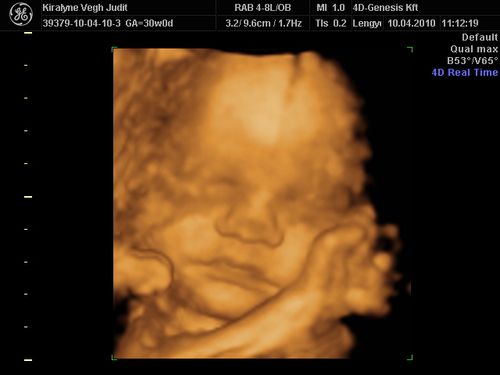

Nagyon édes a kis Izabella, tök jól sikerültek az UH képeid, nagyon fotogén a csaj!:)